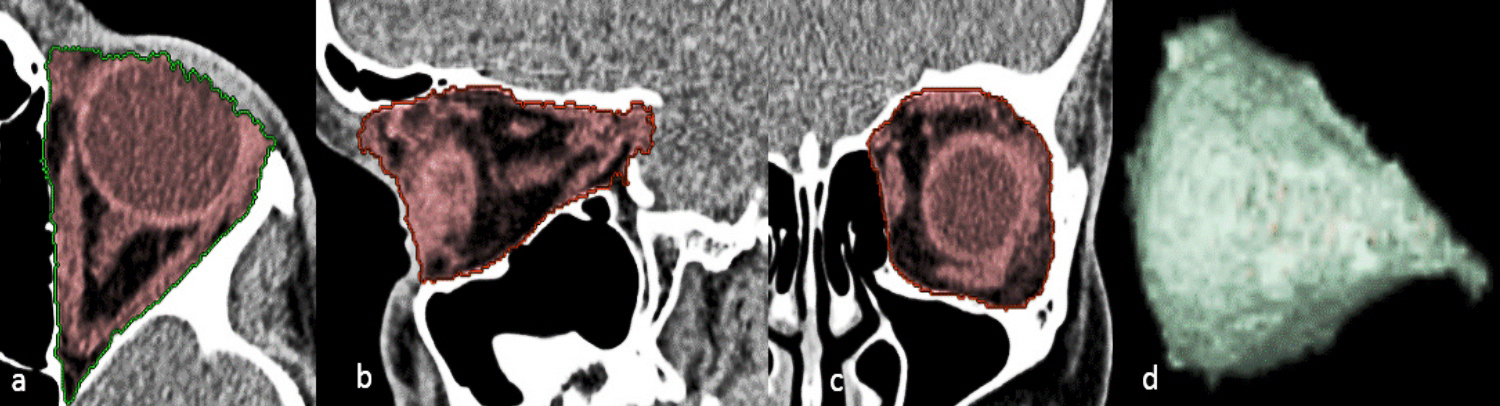

For every child, OV was calculated by a 3D-assisted semi-automated volumetric methodology using the 3D volume rendering tool (VR).2,3 This method includes a mixture of manual segmentation performed using seed-growing algorithms with contour constraining, using the three-dimensional reconstructed images then rendering software volume calculation with a graphic representation of the 3D configuration of the orbital cavities (Figure 1). This 3D Volume VR tool is available on Advantage Window. The program displays axial, coronal and sagittal images on the same display screen. The measurement area of the orbit ranged from the lacrimal fossa to the optic canal. A straight line through the lateral and medial orbital rims defined the anterior border of the orbit. The posterior limit was set at the opening of the optic foramen into the orbit. On the axial slice, the ‘‘VR tools, add segment, auto select tool, any structure, was selected and the ‘‘threshold’’ was set between 0 and 160 with the window width 300, window length 35 HU (Hounsfield unit), then the orbital contents were traced and marked using a digital mouse and by left-clicking, we started at the mid-orbit with the area of interest colored red using autoselection for each slice. Then the slice was scrolled stepwise in a cranio-caudal direction until all the orbital contents of interest were colored. Next, we moved from axial to the sagittal view and then a coronal slice and repeated the same procedure to confirm the most anterior, posterior, superior, and inferior limits using auto-location on a sagittal-plane view. The optic canal, soft tissue and portions of the globe protruding out of the orbital rim were excluded from volume calculation. During tracing, the observer had to work with all three-images as stacks as segmentation performed in one image automatically appeared in the other two due to the three-dimensional visual control of the measurements at any moment during the measurement that allowed the observer to visually check the result of the calculations instead of outlining the structures of interest in every slice.

Figure 1 Computed tomography showing the process of segmentation for OV measurement using 3D -semi-automated volumetric methodology. The highlighted segment of tissue content of the orbit with the boundaries of the bony orbital cavity is denoted by green and the traced orbital content is marked as red and measured in (a, axial b, sagittal c, and coronal images with d, Generated conical shape 3D-reconstruction of the bony orbital contents.